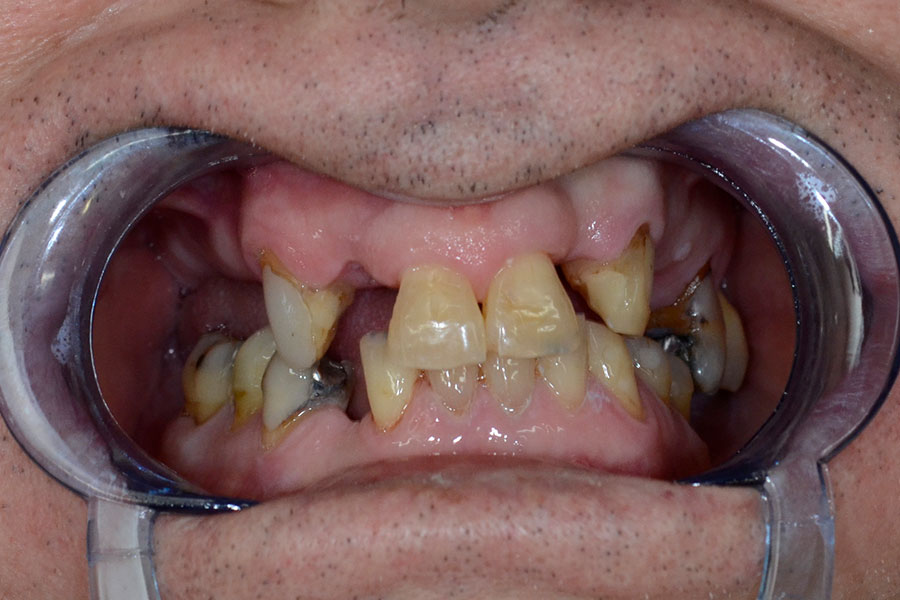

Phil was wearing a removable partial denture for many years.

As he lost some more teeth the pasrtial denture became less stable. Chris finally decided to have dental implants his missing teeth.

Two implants were utilised to support a bridge where there were three missing teeth in a row. His existing natural teeth received crowns and veneers as reinforcements and also to match the highly esthetic implant crowns and bridges.